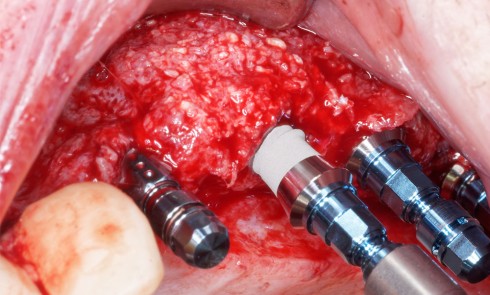

Réalisation des restaurations corono-radiculaires coulées : l’empreinte pour les RCRC sur les 15, 14, 24, 25 et 26 est réalisée selon la wash technique (fig. 8).

Les maquettes en cire pour inlay-core sont ensuite confectionnées (fig. 9). Les inlay-cores sont scellés en bouche (fig. 10), puis une prise d’empreinte des piliers est effectuée selon la wash technique (fig. 11).